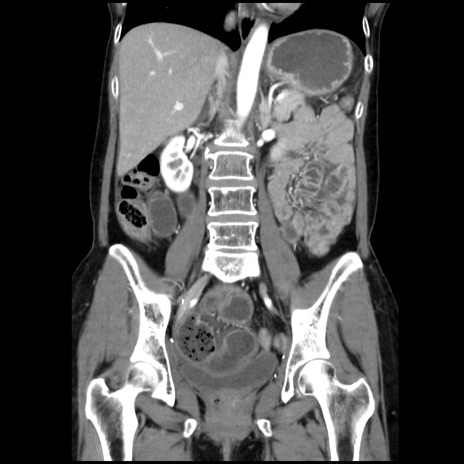

症例32(冠状断像)

【症例】40歳代 女性

【主訴】上腹部痛、嘔気・嘔吐

【現病歴】約9時間前頃から急に上腹部痛、嘔気、嘔吐が出現。改善しないため救急要請。

【既往歴】子宮頚癌(広汎子宮全摘術、放射線療法)、腸閉塞

【身体所見】腹部:平坦、軟、腸雑音亢進、上腹部を中心に腹部全体に圧痛あり。

【データ】WBC 8400、CRP 0.03